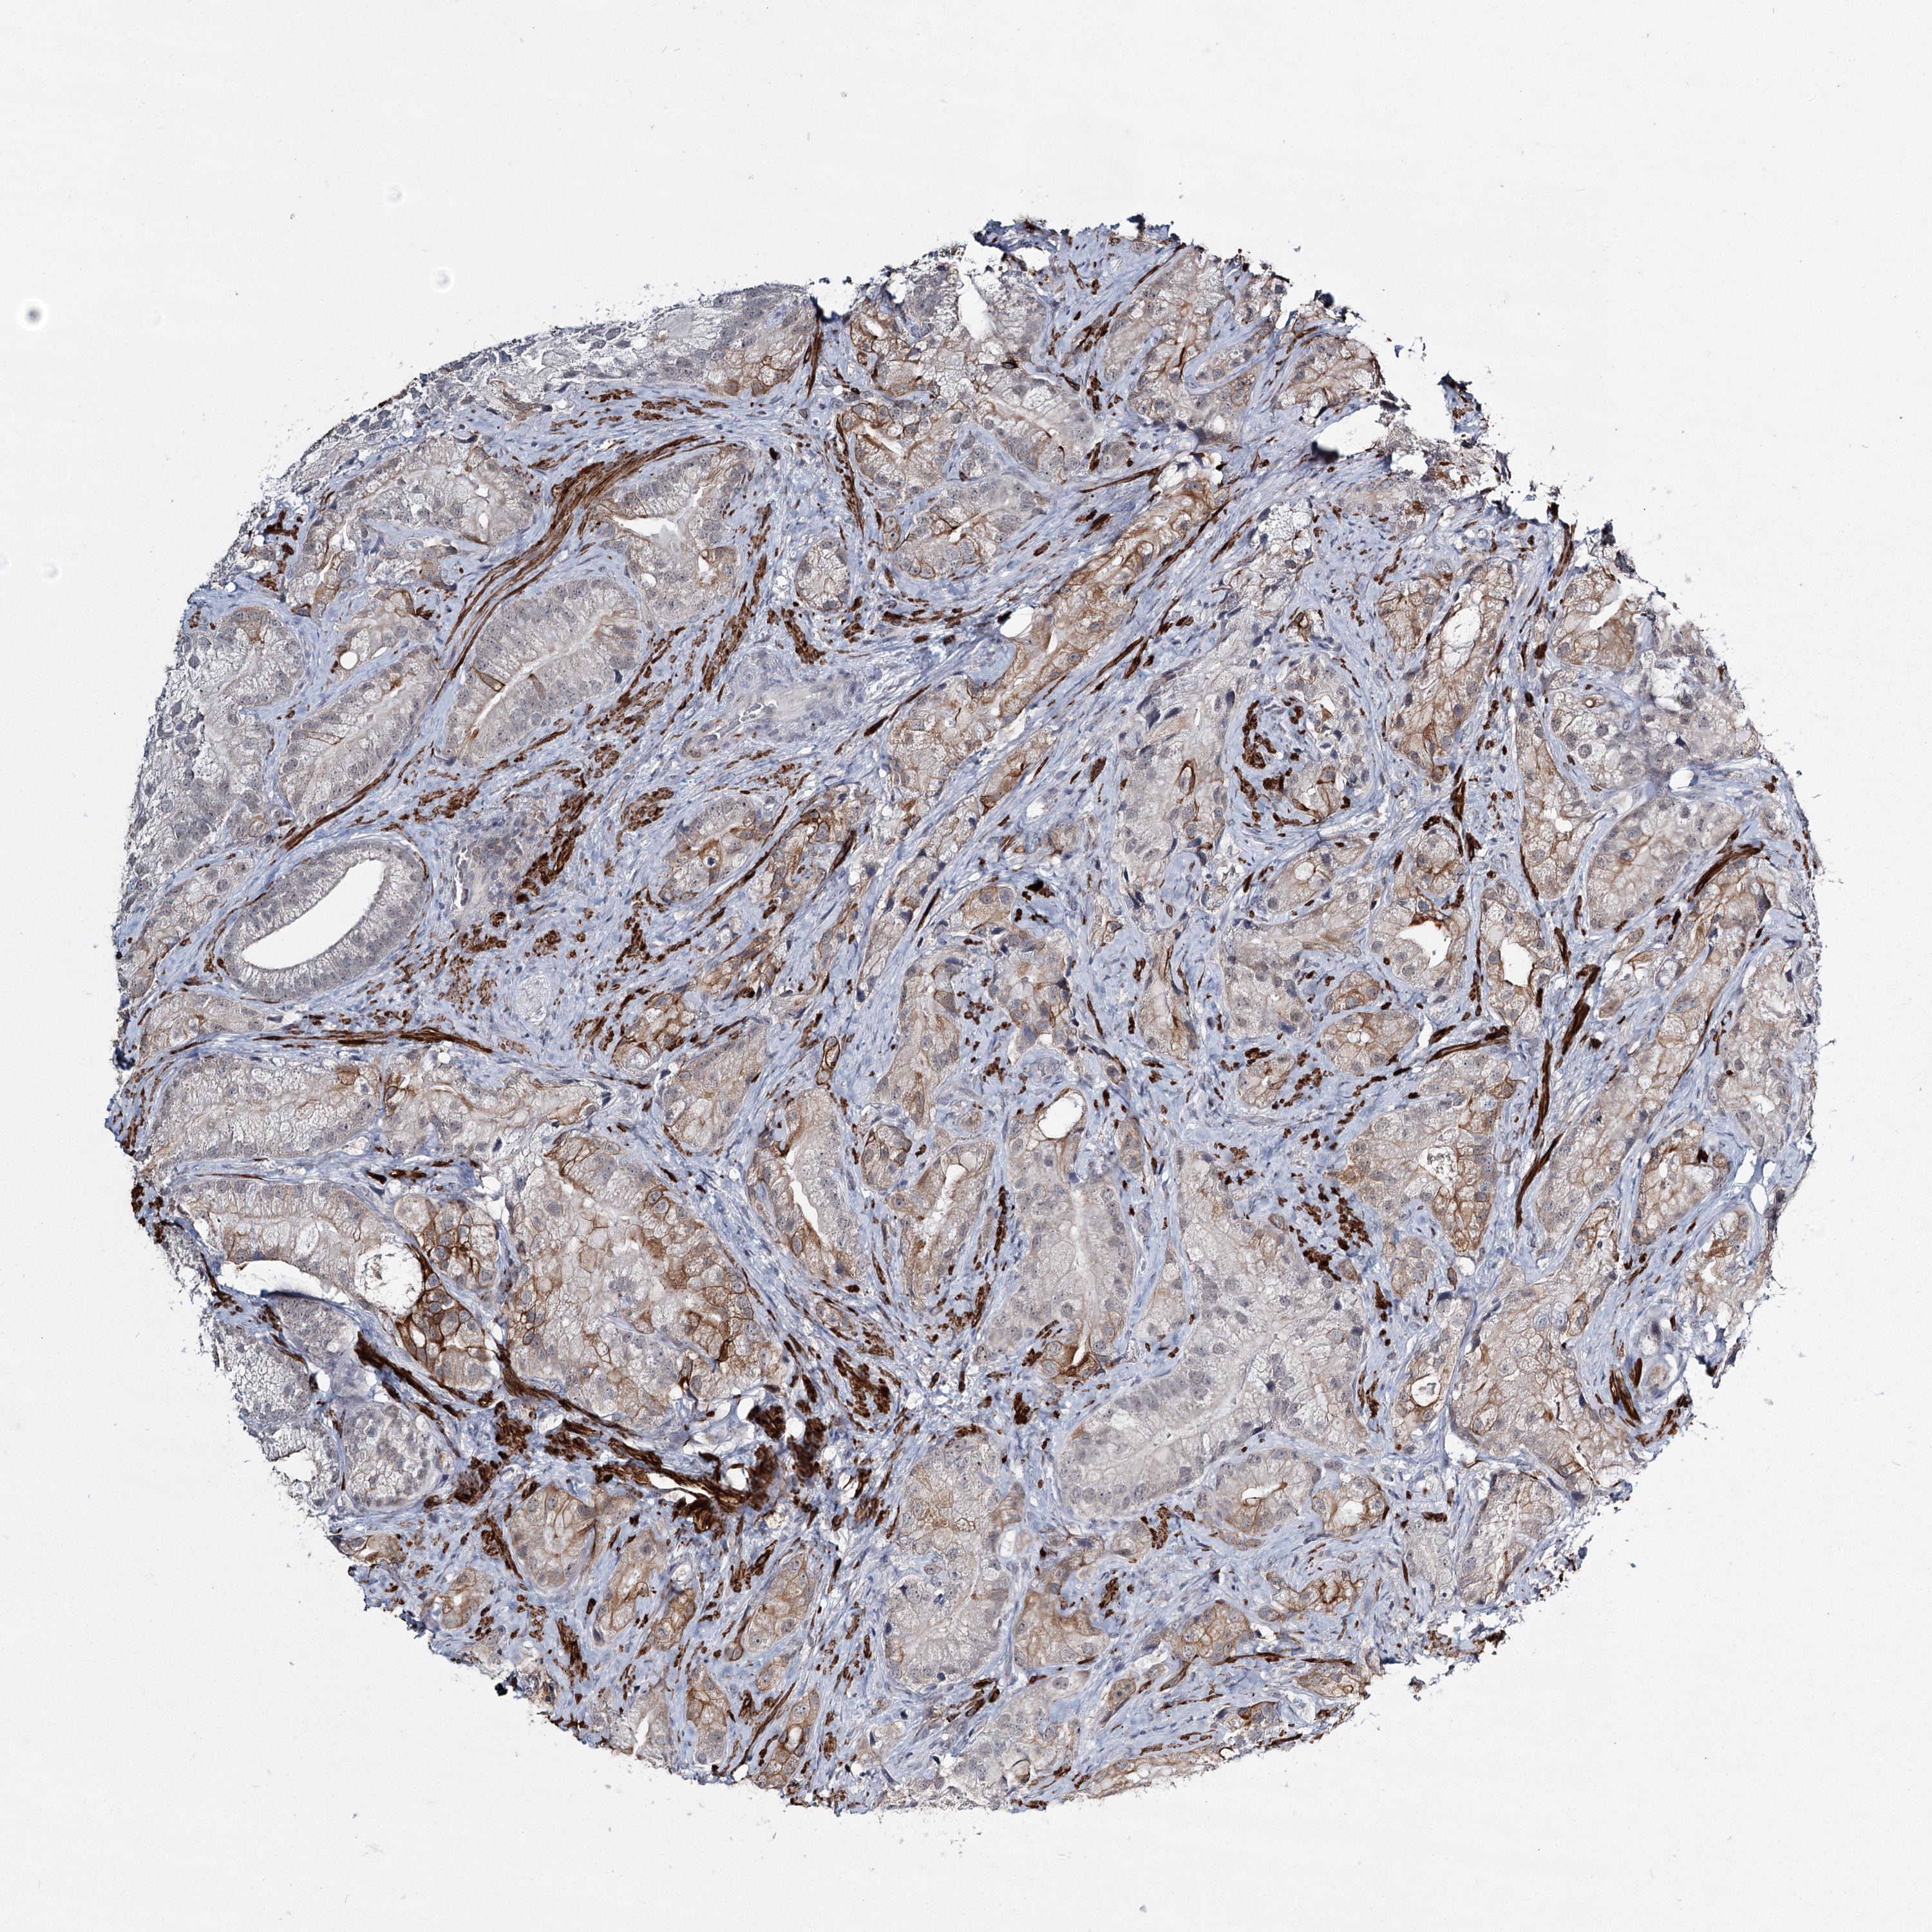

PROSTATE CANCER - Protein expressioni

A mouse-over function shows sample information and annotation data. Click on an image to view it in a full screen mode. Samples can be filtered based on level of antibody staining by selecting one or several of the following categories: high, medium, low and not detected. The assay and annotation is described here.

Note that samples used for immunohistochemistry by the Human Protein Atlas do not correspond to samples in the TCGA dataset.

Antibody stainingi

Antibody staining in the annotated cell types in the current human tissue is reported as not detected, low, medium, or high, based on conventional immunohistochemistry profiling in selected tissues. This score is based on the combination of the staining intensity and fraction of stained cells.

Each image is clickable and will lead to virtual microscopy that enables deeper exploration of all samples and also displays staining intensity scores, fraction scores and subcellular localization as well as patient and tissue information for each sample.

Antibody HPA023187

Antibody CAB034226

Staining

High

Medium

Low

Not detected

Intensity

Strong

Moderate

Weak

Negative

Quantity

>75%

75%-25%

<25%

None

Location

Nuclear

Cytoplasmic/membranous

Cytoplasmic/membranous,nuclear

Adenocarcinoma, High grade

Adenocarcinoma, Low grade

Adenocarcinoma, NOS